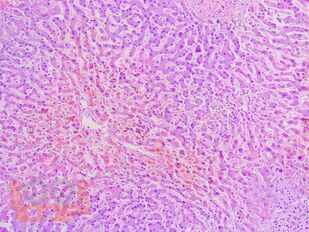

В учебном пособии представлен теоретический материал, перечень макропрепаратов и микропрепаратов, демонстрирующих типовые проявления патологических процессов. В цветных иллюстрациях и в описании микропрепаратов сделан акцент на наиболее важных гистологических изменениях, позволяющих на светооптическом уровне диагностировать и дифференцировать состояния, отклоняющиеся от нормы, в том числе с использованием различных гистологических окрасок. Пособие помогает выделить главные аспекты изучаемых патологических процессов, организовать и конкретизировать учебный процесс.